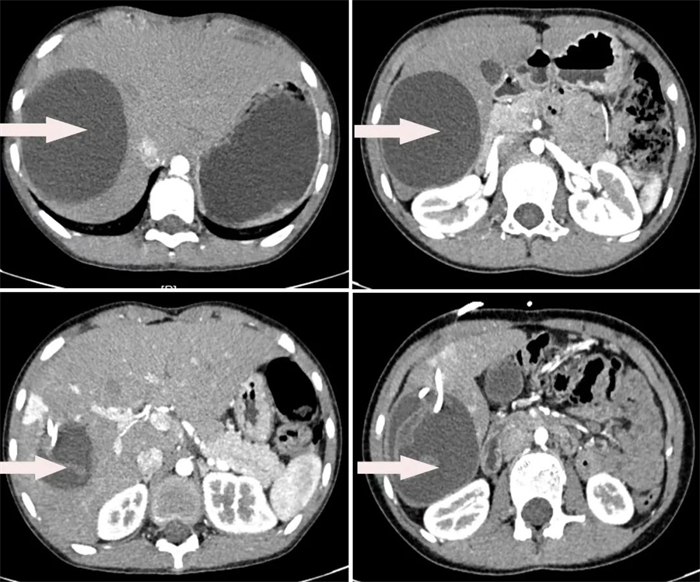

患者2,10岁女性,因“发现肝脏包块4天” 入院,经CT检查提示肝右叶占位性病变,考虑肝细粒棘球蚴病。